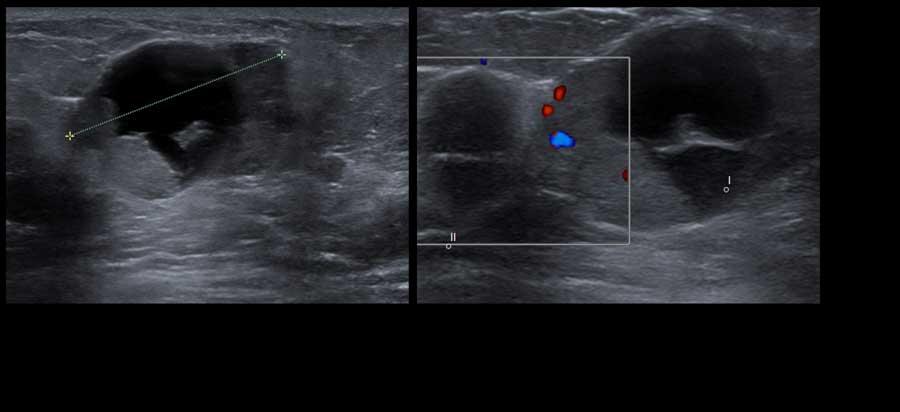

Khối u trong nang

Đôi khi một phần của nang không có hình ảnh trống âm mà lại giảm âm hoặc tăng âm.

Điều này có thể là kết quả của mủ hoặc các mảnh vụn, nhưng cũng có thể là một khối u trong nang như trong các hình ảnh này.

Khối u trong nang là hiếm gặp.

Khi thấy có mạch máu trên siêu âm Doppler màu thì đó là khối u trong nang, có thể lành tính hoặc ác tính.

Đây là một khối u có thành phần dạng nang chứ không phải là một nang đơn thuần.

Trong trường hợp không có dòng chảy trên siêu âm Doppler màu và không có tín hiệu âm mức độ thấp di chuyển khi thay đổi tư thế bệnh nhân, cần thực hiện chọc hút để phân biệt giữa nang phức tạp và khối đặc.

Mủ và các mảnh vụn có thể được hút ra, khác với khối u.

Trong trường hợp này, sinh thiết xác nhận là ung thư biểu mô trong nang.

Đây là một trường hợp ung thư vú khác có thành phần dạng nang.

Lưu ý thành phần đặc lớn với dòng chảy trên hình ảnh Doppler.